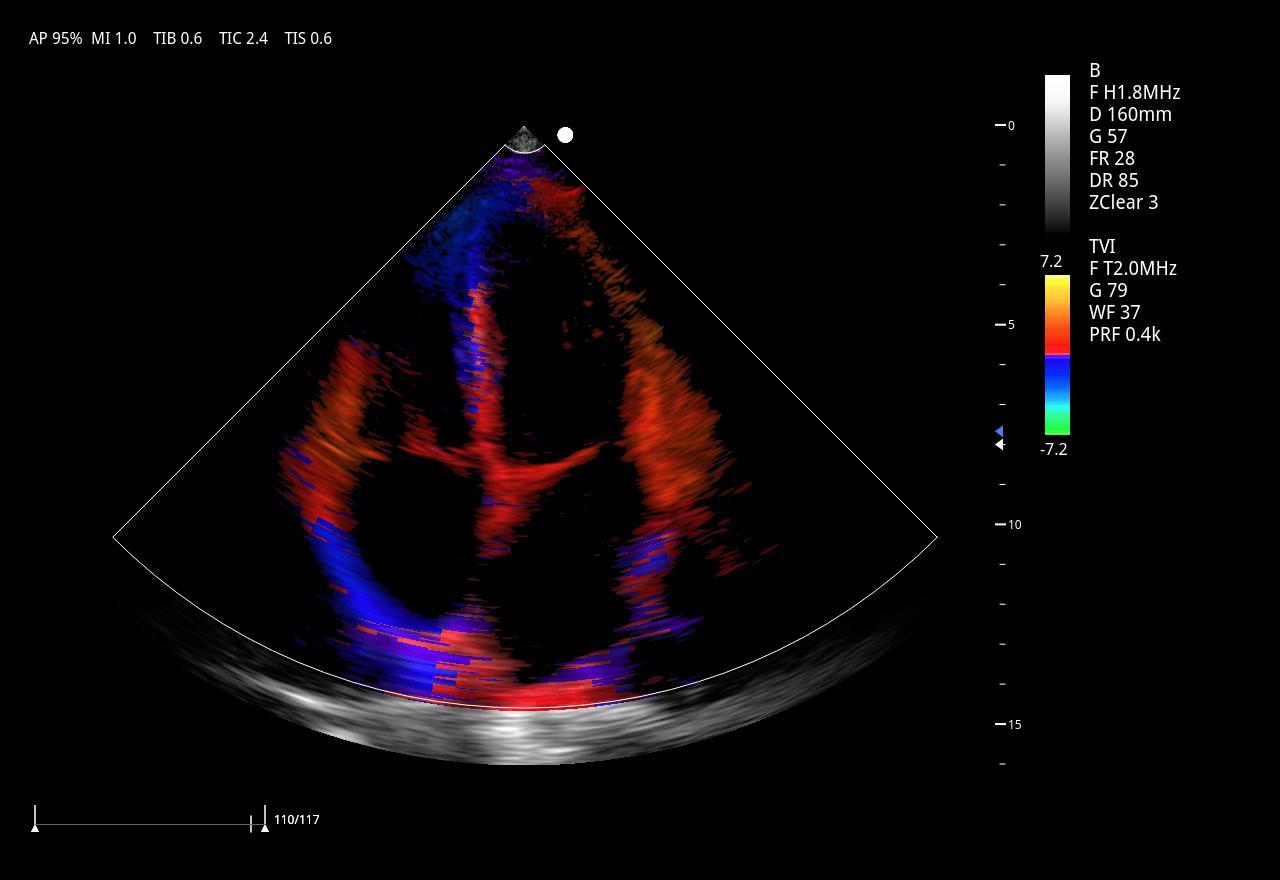

Imágenes clínicas extraordinarias

| Aplicaciones | Cardiología, abdomen, vasos sanguíneos, estudios generales |